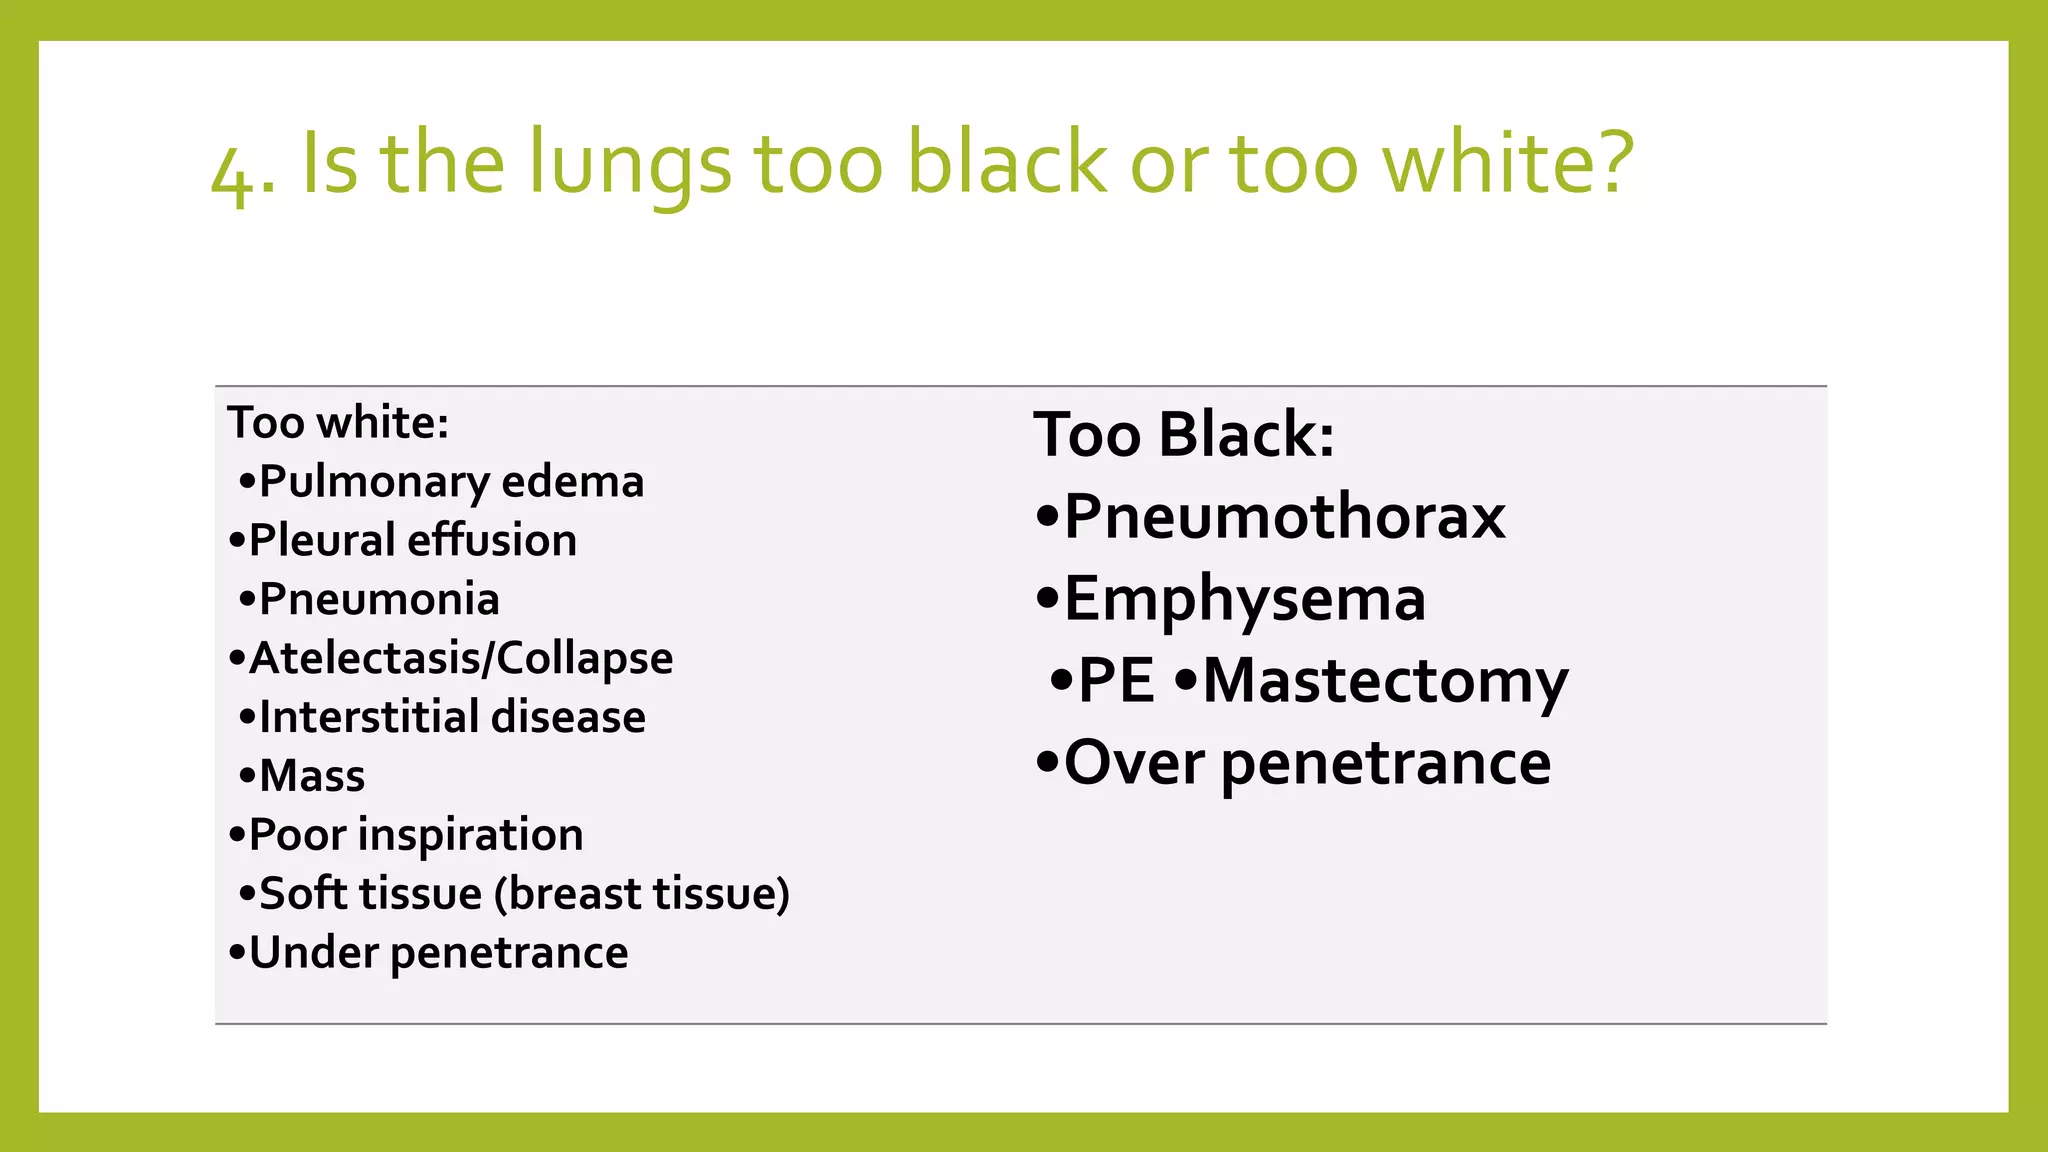

The document provides guidance on approaching and interpreting chest x-rays (CXR). It outlines steps to check the name, date and quality of the film, systematically scan the CXR looking for abnormalities, and determine if the lungs appear too white or black. Specific signs are described to help localize abnormalities, including the cardiac silhouette sign and pleural effusion signs. Examples are given of respiratory distress syndrome, tetralogy of fallot, transposition of great arteries, and total anomalous pulmonary venous return. The take home message is to summarize positive findings, compare to prior CXRs if available, and confirm findings with a radiologist.